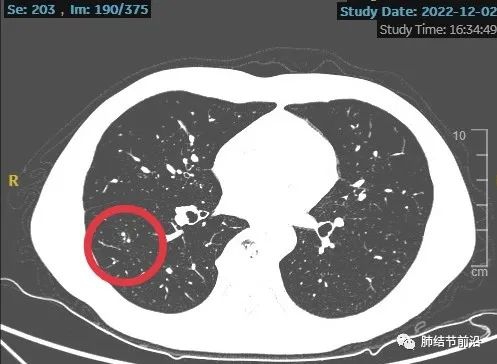

患者口服头孢治疗2周,后三个月复查来诊。薄层CT显示,右下肺磨玻璃结节变成了相邻的数枚实性小结节。

磨玻璃变实性,患者很担心。但是从这个结节的发展过程,基本可以排除恶性。告知患者不用紧张。

另外,CT显示为靠近胸膜,斑斑点点的相邻病灶,不符合结核卫星灶,符合隐球菌感染表现。